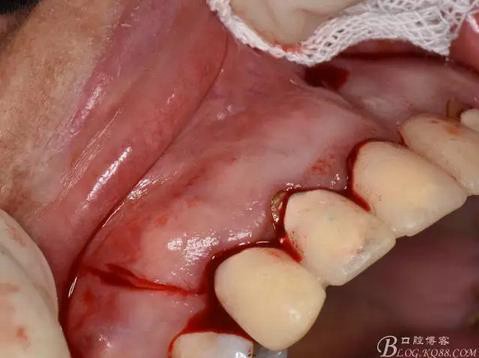

圖7. 分別在13的遠中和11的近中做垂直切口加齦溝內水平切口,形成梯形瓣

圖8.翻開梯形瓣